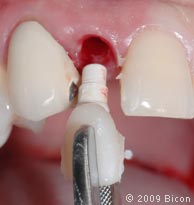

29. Удаление излишков мягких тканей, которые могут препятствовать правильной установке трансфера, производится посредством слепочного римера размером 3 мм, вращаемого вокруг направляющего штифта.